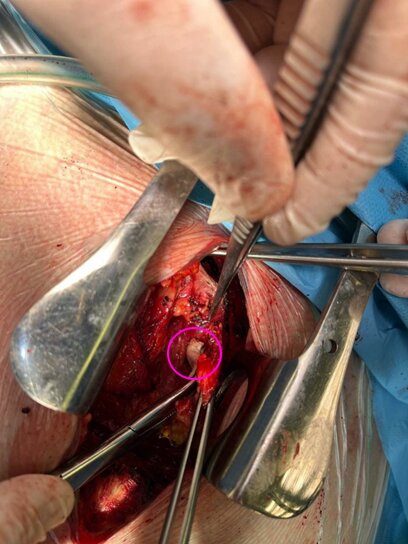

Рисунок 4. Процесс удаления инородного тела через J-образную министернотомию.

07.03.2024г. выполнили J-образную министернотомию, при ревизии выявили металлический осколок цилиндрической формы размерами 8х6 мм, который интимно прилегал к дуге аорты и левой плечеголовной вены. Осколок был удален, а ложе обильно промыто растворами антисептиков.